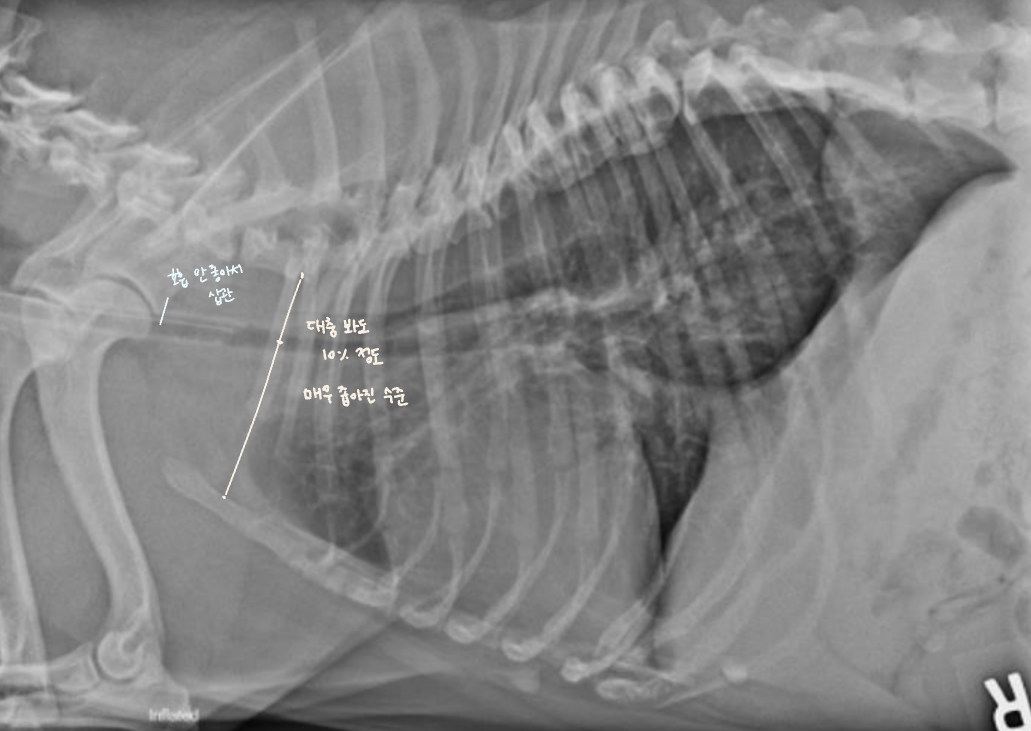

Tracheal hypoplasia

| Tracheal hypoplasia |

|---|

| ๊ธฐ๊ด ์ง๊ฒฝ์ ๊ฐ์, ๋จ๋์ข

์์ ํํจ - Bulldog์ ์๋ ์์์ 9% ์ดํ๋ถํฐ ์ด์ ์๊ฒฌ - ๊ธฐ๊ด์งํ๋ ด(Bronchopneumonia) ๋ค๋ฐ - ๋ค๋ฅธ ์ ์ฒ์ ์ด์, ์ฌ๋ฐ๋ ํํจ - ๊ธฐ๊ด์ด ๋ง๋ ค๋ค์ด๊ฐ๋ฉด์ ์ข์์ง๊ธฐ ๋๋ฌธ์ cilia ๊ธฐ๋ฅ X, ๊ธฐ๋ฅ์ ์ผ๋ก๋ ๋ง์ด ๋จ์ด์ง |